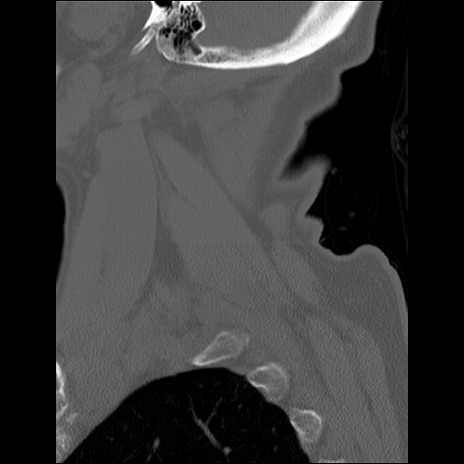

症例48 頚椎CT(矢状断像)

頚椎CT